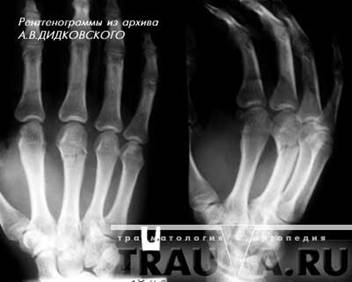

Тайны медицины: Перелом в двух проекциях